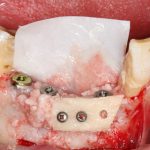

Рекомендации по установке имплантов. Для всех. Часть V.